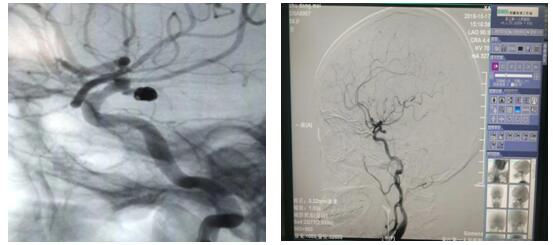

介入栓塞术是通过股动脉穿刺,将纤细的微导管放置于动脉瘤囊内或瘤颈部位,再经过微导管将柔软的钛合金弹簧圈送入动脉瘤囊内或瘤颈部位并将其填充,使得动脉瘤囊内血流消失,促进瘤内血栓形成,治愈动脉瘤。

近日,56岁的朱女士因“左侧面部麻木2天”入院,完善颅脑磁共振及头颈部CTA检查,示左侧颈内动脉与大脑中动脉交界处动脉瘤。DSA检查后,明确诊断“动脉瘤、动静脉畸形”瘤体大小为4-5mm,患者存在病灶侧动眼神经麻痹,考虑瘤体压迫所致,经苏大附二院肖国栋主任会诊后在全麻下行DSA脑动脉瘤栓塞术,整个手术过程顺利,全程用时1.5小时,患者麻醉苏醒后安返病房,经护理人员精心护理,目前患者病情平稳,在积极康复中。颅内动脉瘤介入栓塞术在金沙娱乐城app是首次开展,手术的成功完成标志着金沙娱乐城app神经内科脑血管介入治疗又登上了一个新台阶。同时,也填补了金沙娱乐城app在这一领域的空白。